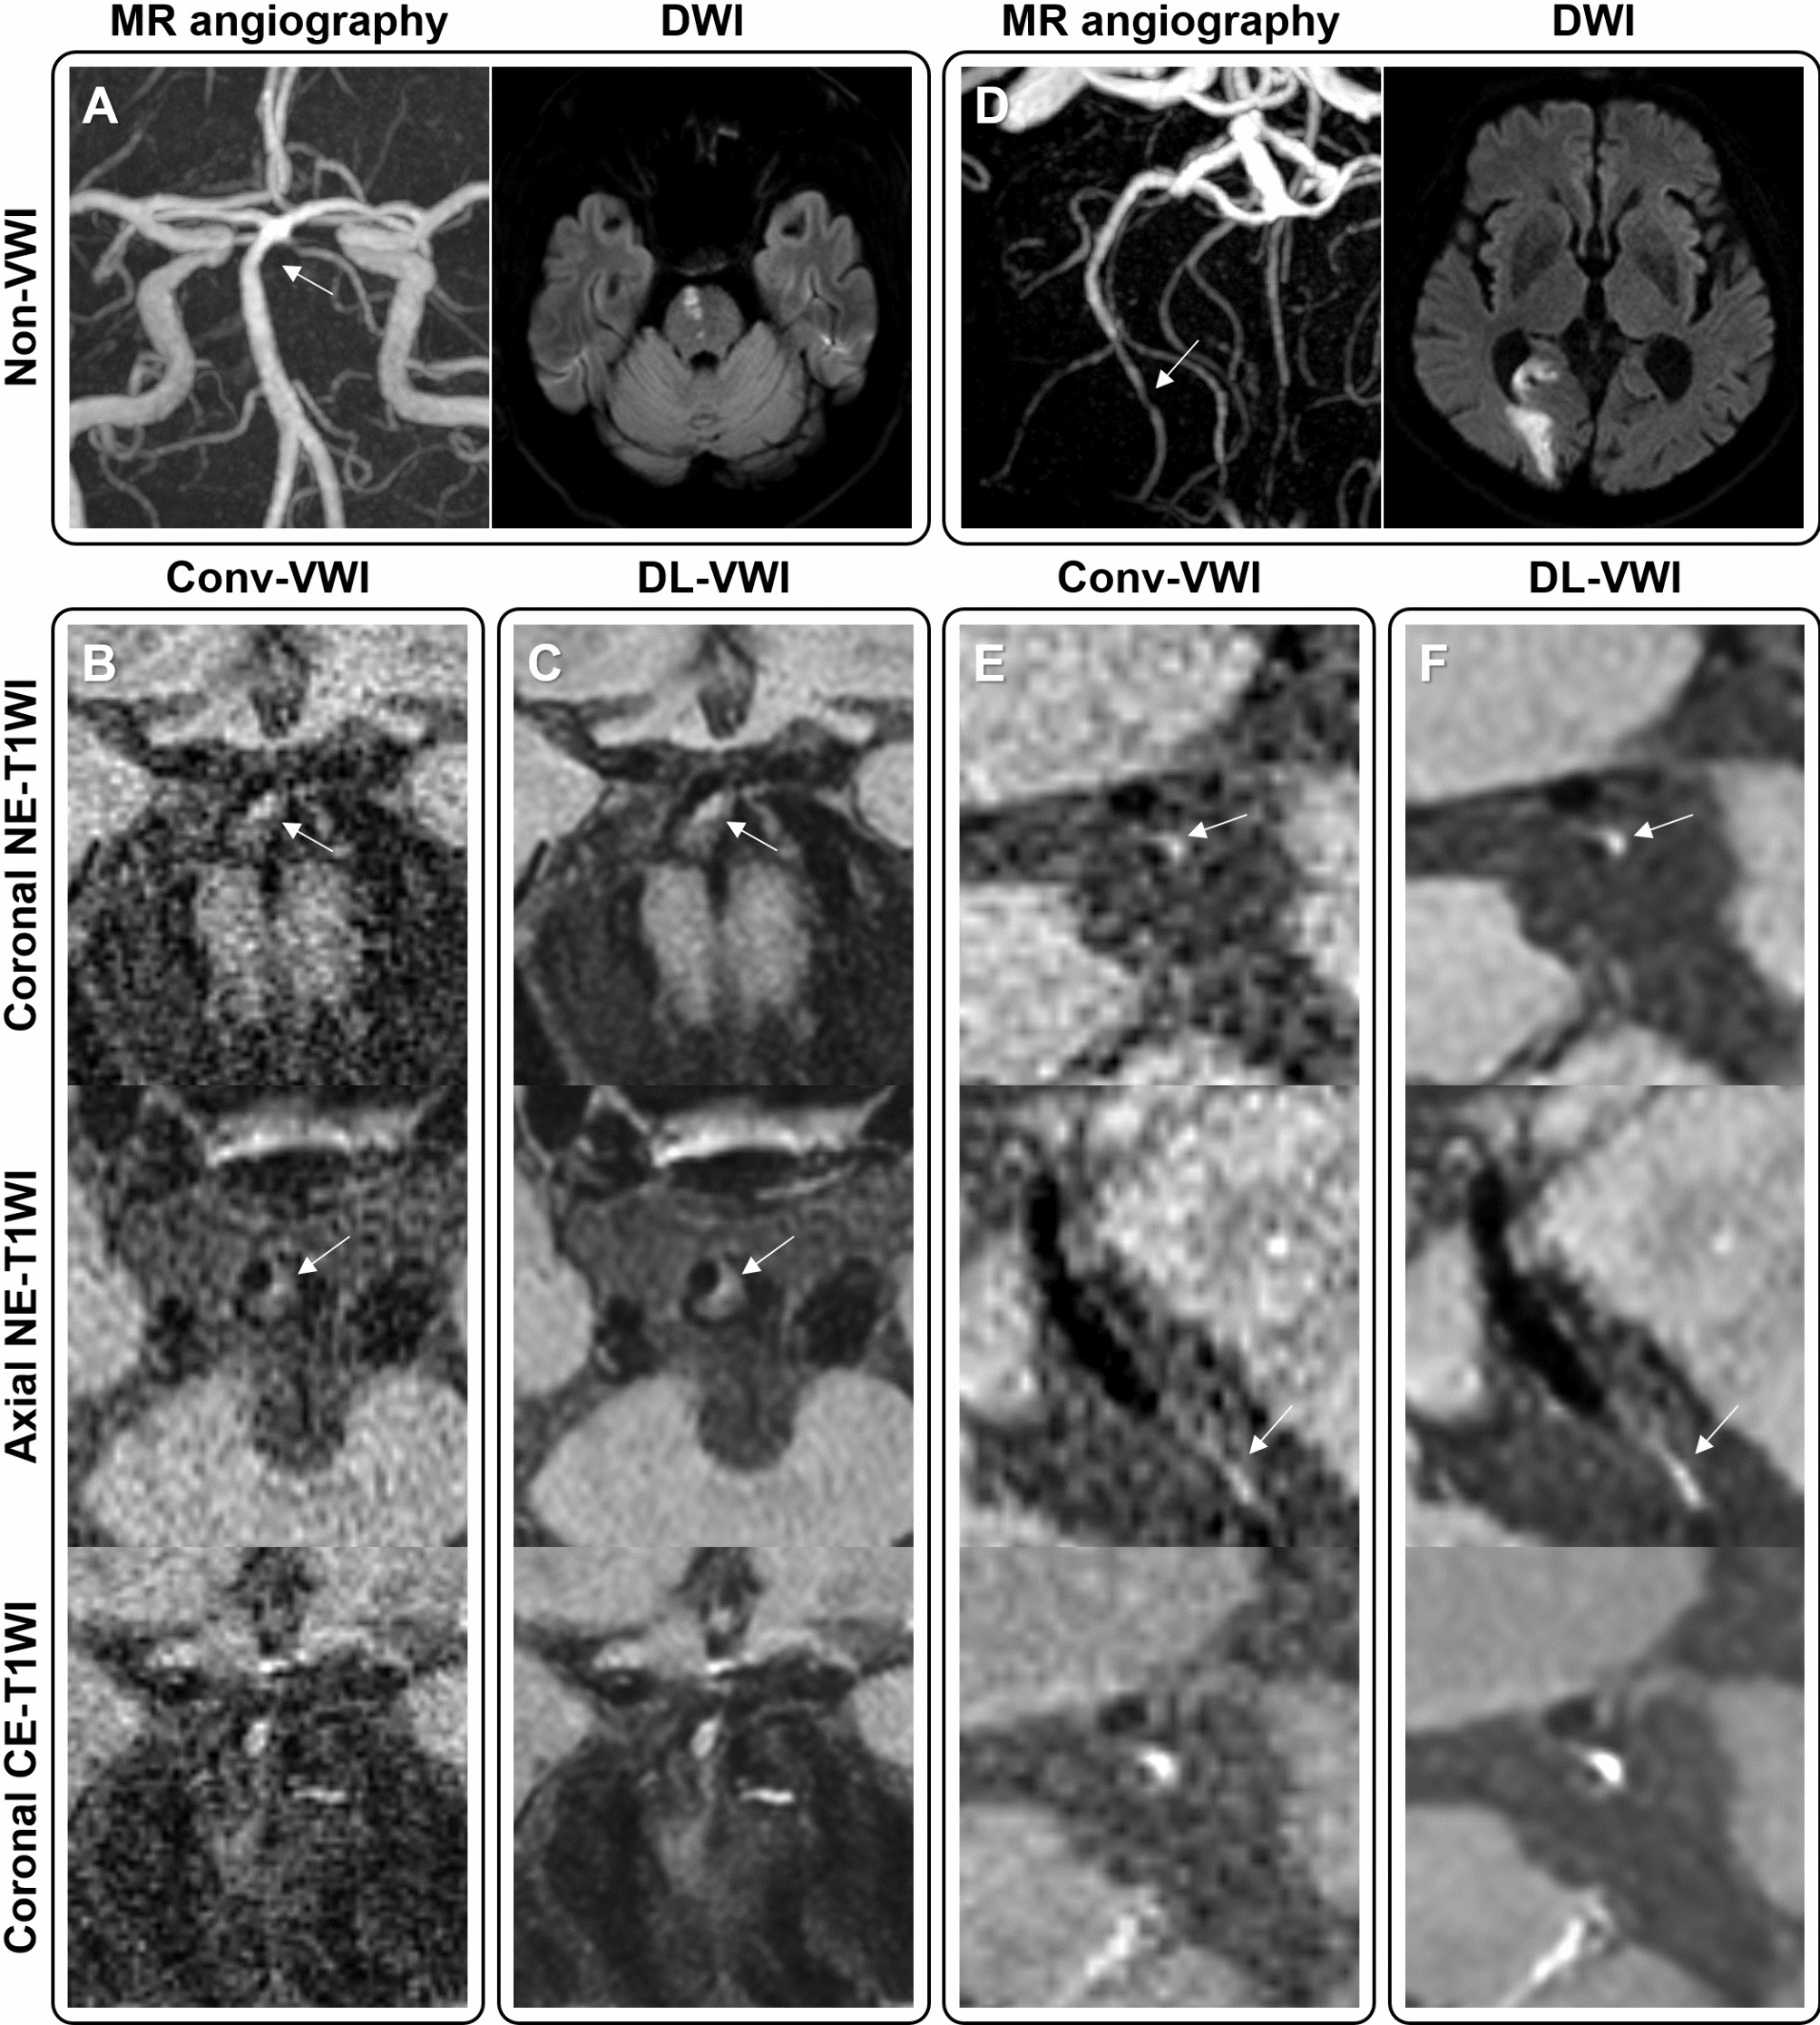

Figure 4

Two illustrative cases of potentially culprit plaques. (A) In a 62-year-old male with abrupt dysarthria and pontine infarct, only mild distal basilar stenosis was identified on MR angiography. (B) Conv-VWI revealed the plaque with punctate T1WI hyperintensity, which was interpreted as an intraplaque hemorrhage (IPH) by only one reviewer. (C) DL-VWI more clearly depicts the apparent T1WI hyperintensity and positive remodeling. (D) Another 66-year-old male presented with abrupt left homonymous hemianopia, showing right posterior cerebral artery territory infarct with focal distal stenosis. (E) Same as Fig. 1, the signal of the plaque in Conv-VWI was misinterpreted as image noise by both reviewers. (F) DL-VWI provides a clearer depiction of the presence of IPH.